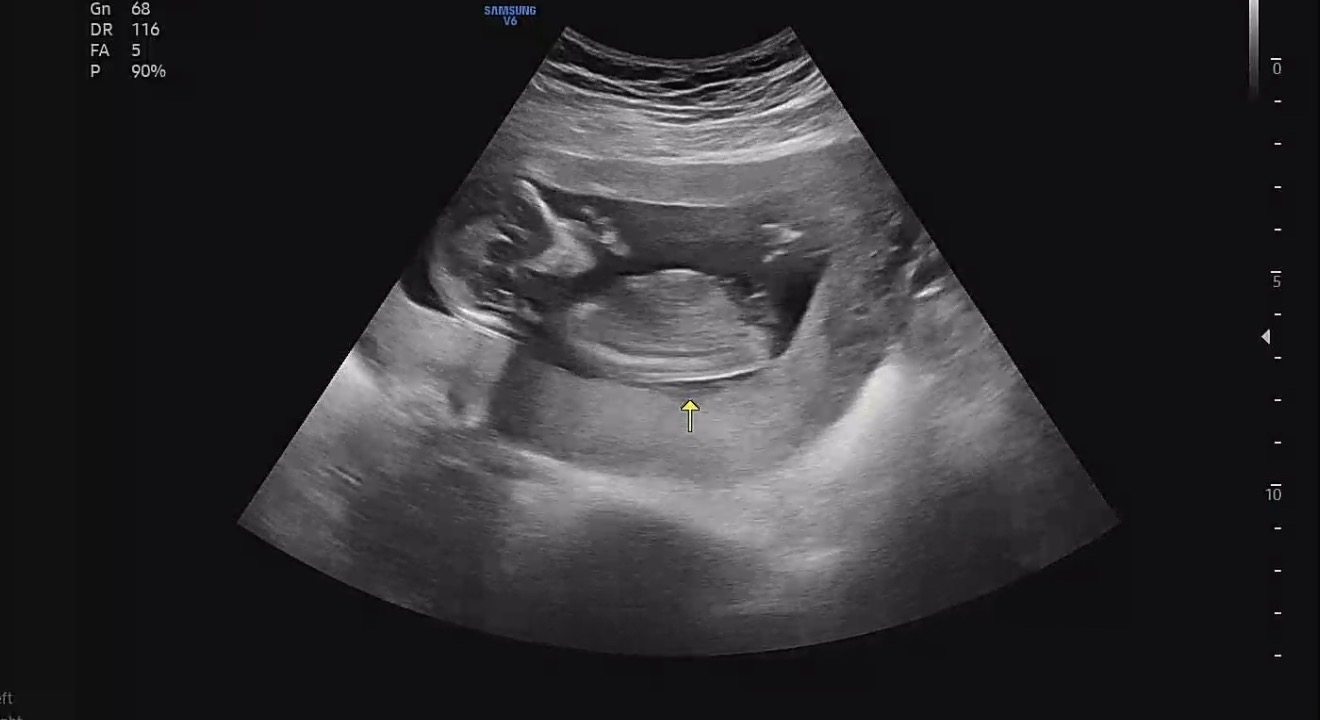

각도법봐주세용

13주4일입니당 병원에서는 확실하지는 않지만 딸같다고 해주셨어요!